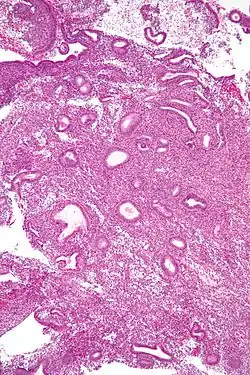

Die einfache Hyperplasie besteht aus zystisch erweiterten Schleimhautdrüsen (Schweizer-Käse-Muster) mit reichlich Bindegewebe (Stroma) zwischen den Drüsen.

Die komplexe Hyperplasie ist durch eine Zunahme des Drüsen-Stroma-Verhältnis gekennzeichnet. Außerdem sind die Drüsen durch Aufzweigungen und Knospungen unregelmäßiger gestaltet.

Die atypische Hyperplasie weist zusätzlich zu den Veränderungen der Gewebsarchitektur Veränderungen auf zellulärer Ebene auf: abgerundete, blasse Zellkerne, große Nucleoli.